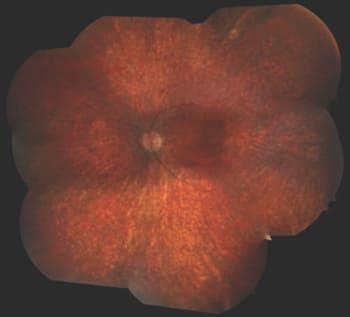

Patient 5 (RDH12)

Patient 5 was first seen at the age of six months because the parents suspected a visual deficit due to a lack of eye contact and the presence of nystagmus. On funduscopy, no abnormalities were noted, and ERG showed reduced cone and absent rod responses. The fundus pictures at age seven are shown in Figure 9.

Figure 9. This fundus image of a patient with mutations in RDH12 taken at nine years of age shows optic disc pallor and attenuation of the vessels. There is a maculopathy and bone-spicule like pigmentation outside of the arcades. Note the peripapillary sparing of the RPE.

Patient 5 has disease due to mutations in RDH12. Patients can have VA as poor as 20/500 and are emmetropic or mildly hyperopic. Visual fields are measurable and are relatively spared in the early years. The retinal abnormalities are visible early in life and are progressive, leading to an early RP-like fundus. All patients show macular atrophy but with peripapillary sparing of the RPE. Taken all together, the phenotype is particularly close to early onset retinitis pigmentosa.

Optical coherence tomography in patients with mutations in RDH12 has shown abnormal thinning of the fovea. As for therapeutic options, recent protein studies have shown evidence for proteasome inhibitors and chemical chaperones to rescue the activity of one RDH12 mutation.13